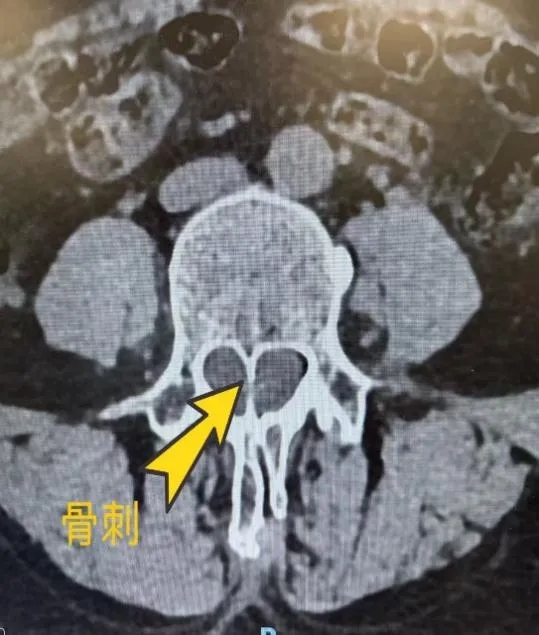

科室依托医院强大平台,以“精准诊疗、微创技术、患者至上”为核心理念,聚焦颅脑创伤、颅脑肿瘤、脊髓脊柱疾病、昏迷促醒以及阿尔兹海默症(老年痴呆)、脑血管病等神经外科领域常见及疑难疾病,致力于为患者提供安全、高效、个性化的诊疗服务。开放床位30张,其中监护病床9张,共有医护人员19名,主任医师1名,副主任医师2名,主治医师2名,医学博士1名,硕士4名;护理人员10余名。

神经外科是医学领域中技术含量高、挑战性强的核心学科之一。我科集临床、教学、科研于一体,专注于脑、脊髓及周围神经系统各类疾病的诊断与治疗,包括但不限于: